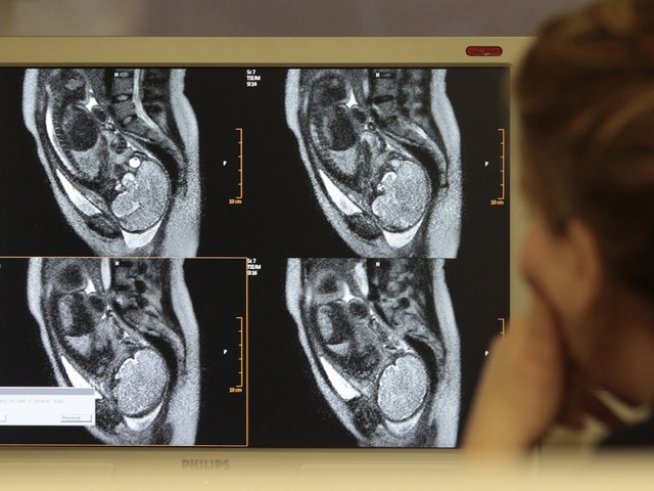

Снимка: Reuters